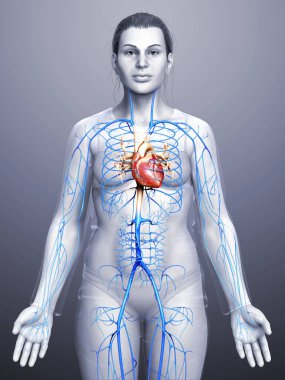

Kalbin anatomik incelemesi. Kalp sorunları, kalp krizi. Ameliyat mı? 3D görüntüleme. Siluet. Kalp, dolaşım sisteminin kan damarlarına kan pompalayan kaslı bir organdır.

Kırmızıİzole edilmişİnsanSağlıkBaşıİlaçSağlık hizmetlerierkekTıbbidikkatAdamsiyahYapıKardiyolojikalpHastagövdeKarnıEğitimİçeridebiyolojiBilimSistemGöğüsSaldırın!AcıorgvenKasÇizelgeİskeletanatomiKas gücübeyindiyagramBilim kurgux ışınısindirimAğrıKardiyakiskeletanatomikkoronerkalp krizi3d oluşturmakaslı organBenzer İçerikler